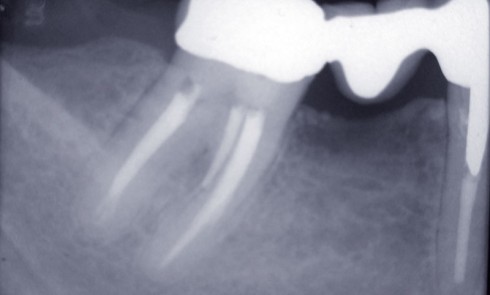

Indications prophylactiques (antibioprophylaxie) L’antibiothérapie prophylactique consiste en l’administration d’un antibiotique dans l’objectif de prévenir le développement d’une infection locale, générale...